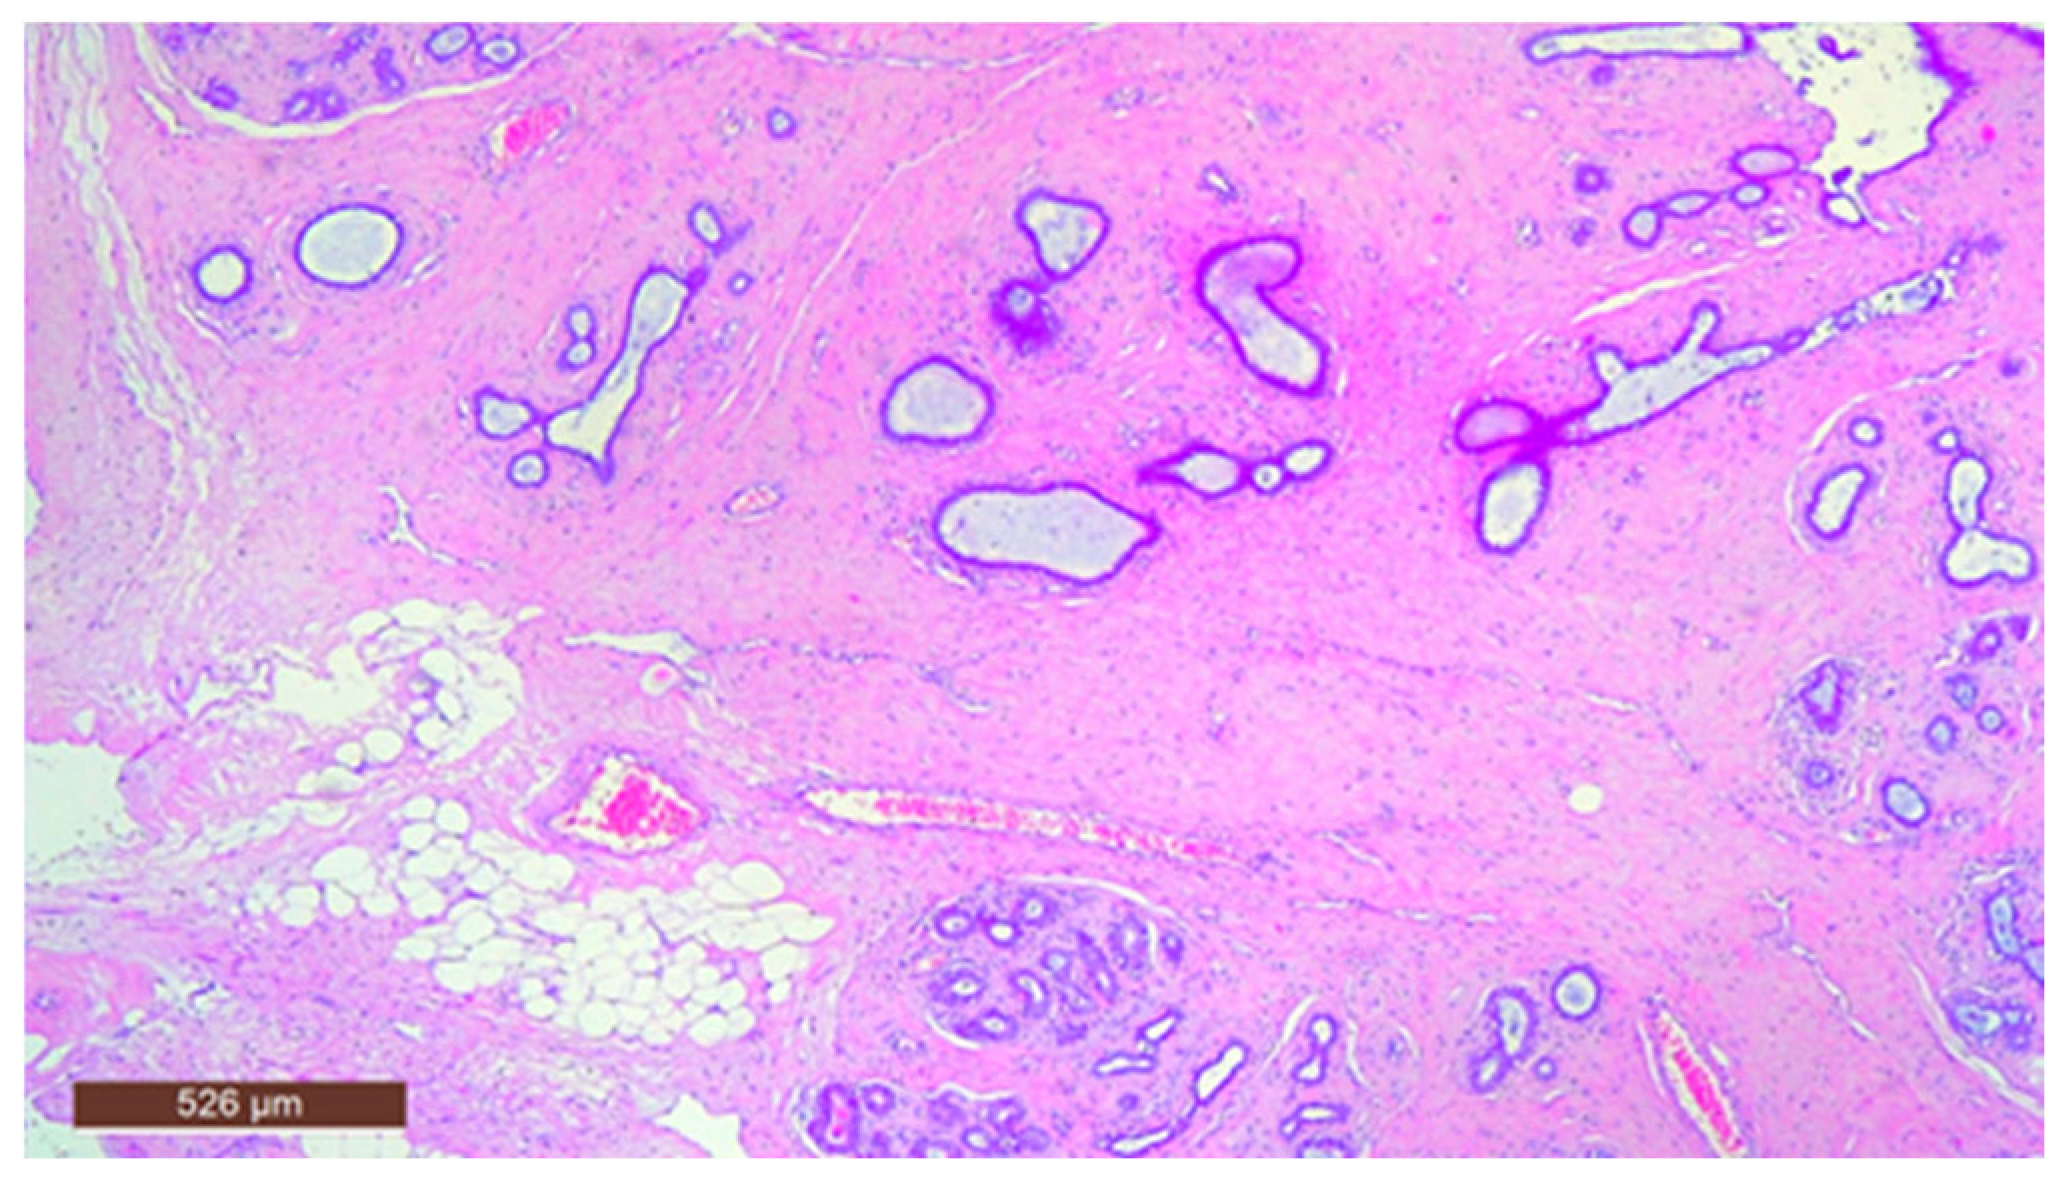

In some instances, fibrous tissue may predominate (Figure 12). Additionally, three cases in our study were associated with chronic inflammation. In the series of 13 cases, no cases with associated malignancy were observed.

Figure 12.

Hamartoma with prominent fibrous tissue (HE ×40).